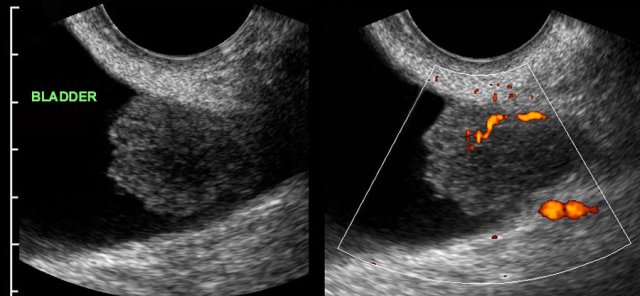

Malignant bladder polyp: coincidental finding by gynaecologist. Malignant bladder polyp: coincidental finding by gynaecologist.

Bladder carcinoma

During routine TVUS, the gynaecologist detected a solid, well-vascularized, moderately well-defined mass with a diameter of 2.5 cms, arising from the bladder wall.

There was no history of hematuria or micturition problems.

Cystoscopic surgery revealed a grade 1 transitional cell carcinoma.